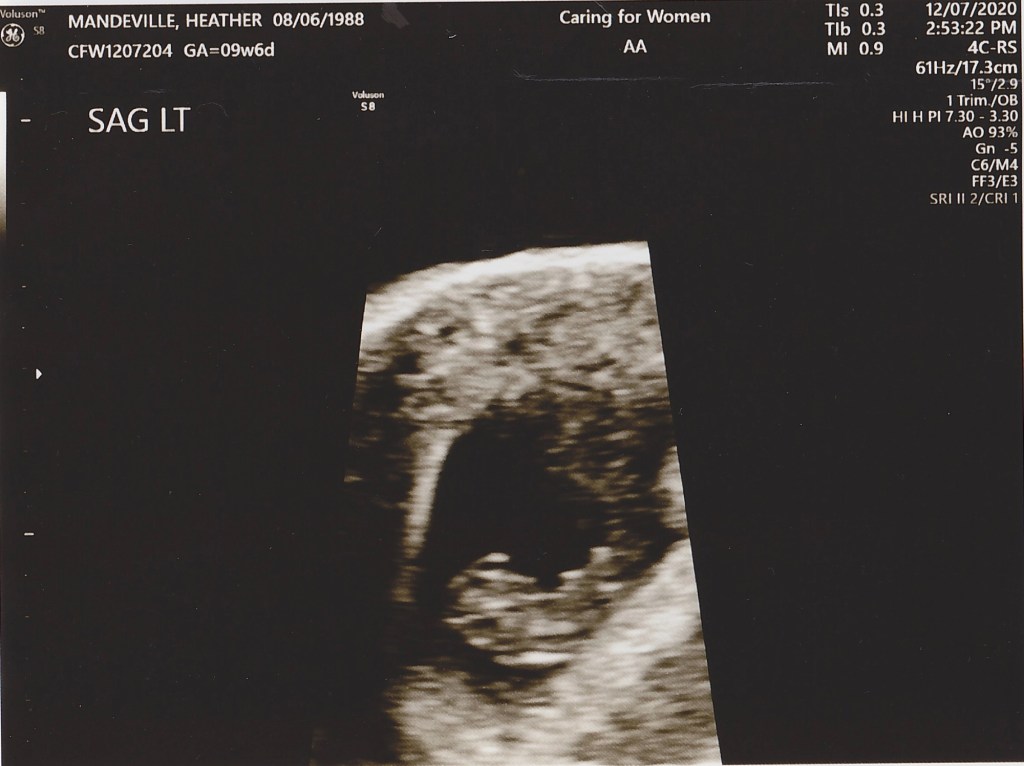

Heathers First Ultrasound!!

The first picture of our little one, only 9 weeks old at this point! We cannot wait to meet him/her in person!!